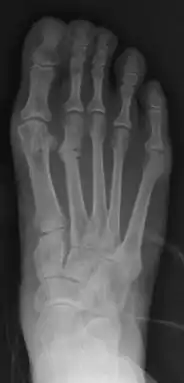

| Stress fracture of the second metatarsal bone | |

X-ray is seldom helpful, but a CT scan and an MRI study may help in diagnosis.[5] Bone scans are positive early on. Dual energy X-ray absorptiometry is also helpful to rule out comorbid osteoporosis.[6]